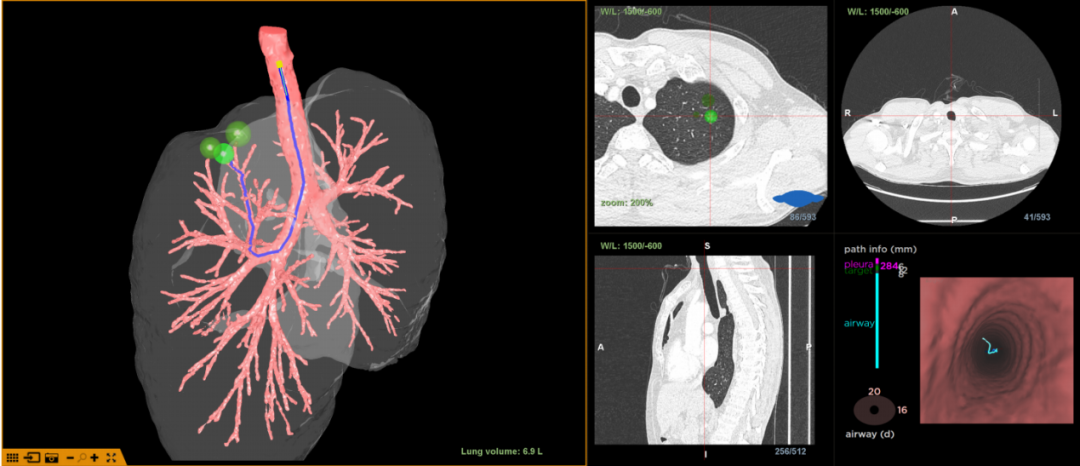

经LungPro增强现实光学全肺诊疗导航系统评估分析,患者病灶位于左肺上叶尖段,大小约8*10mm,临近胸膜。为方便定位,明确诊断,呼吸与危重症医学科边翠霞主任团队与胸外科蔡海波主任团队决定应用LungPro增强现实光学全肺诊疗导航系统引导下在气道注射亚甲蓝进行病灶染色定位,然后行胸腔镜下外科手术。

术中进镜顺利,LungPro增强现实光学全肺诊疗导航系统引导支气管镜至左肺上叶尖段远端细支气管,注药导管依据导航进入相应部位并注入亚甲蓝染色液。随后胸腔镜下根据染色点快速定位。